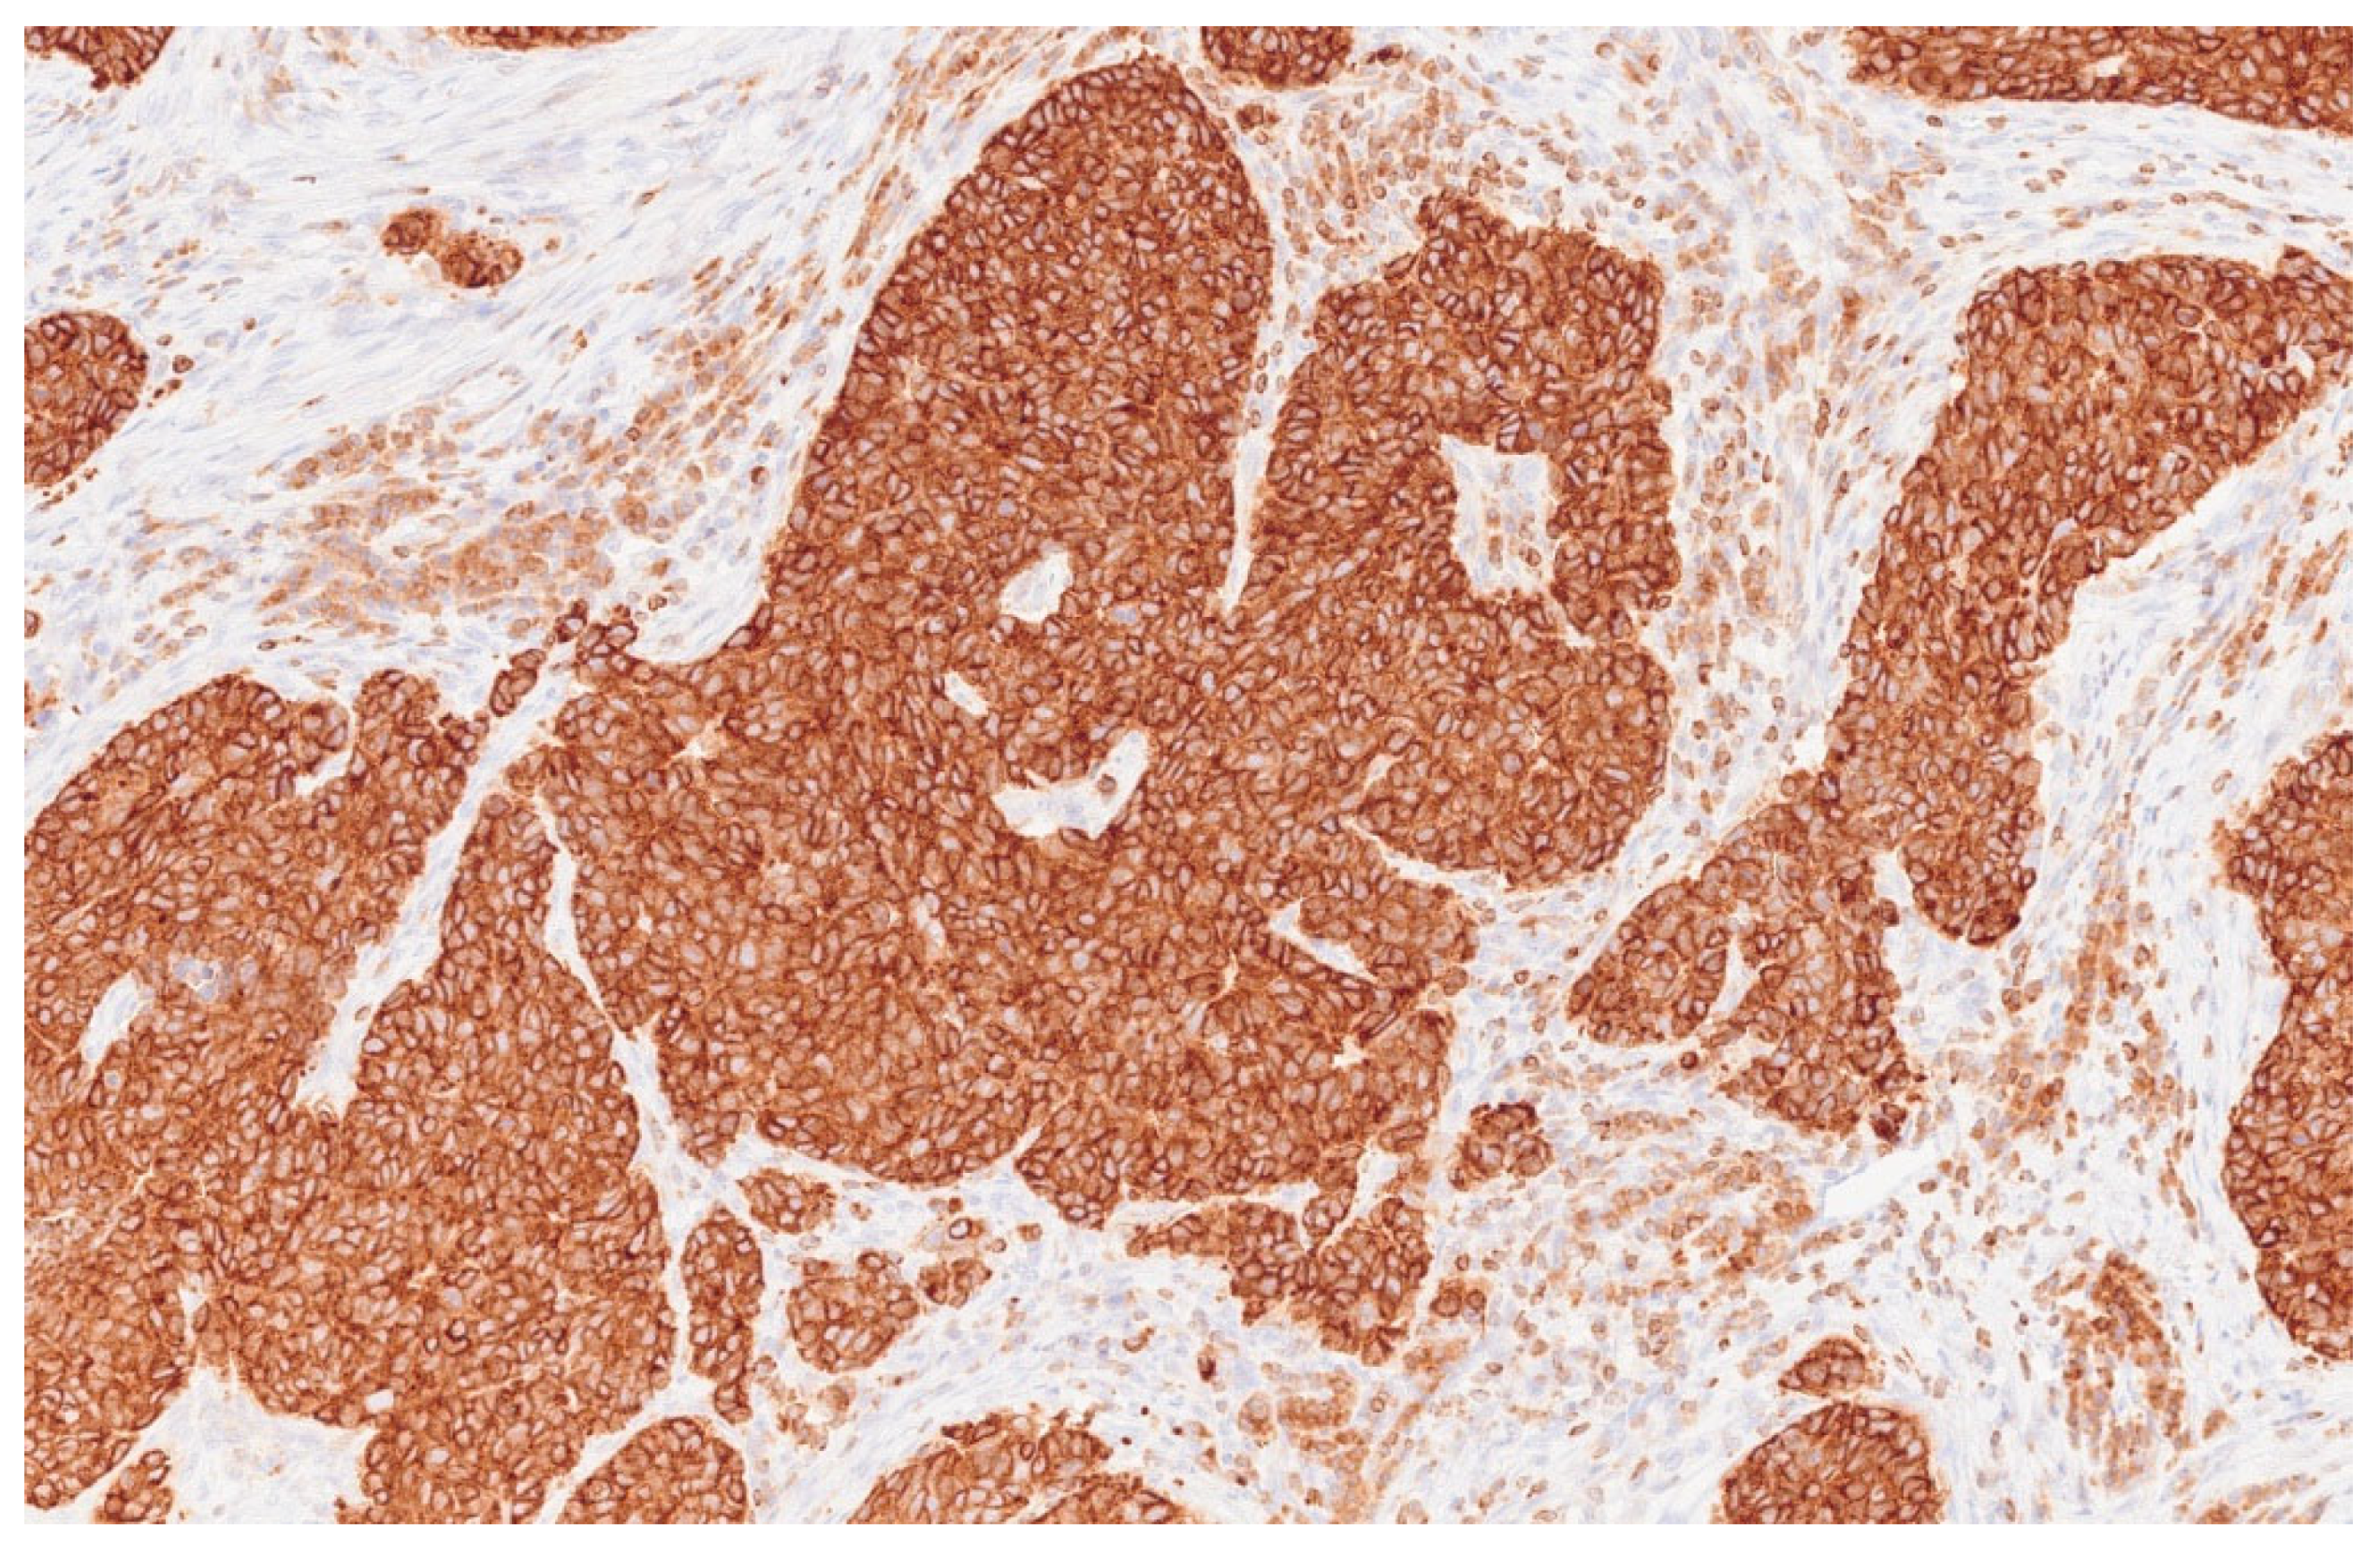

| 3 | Microlaryngoscopy with biopsy |